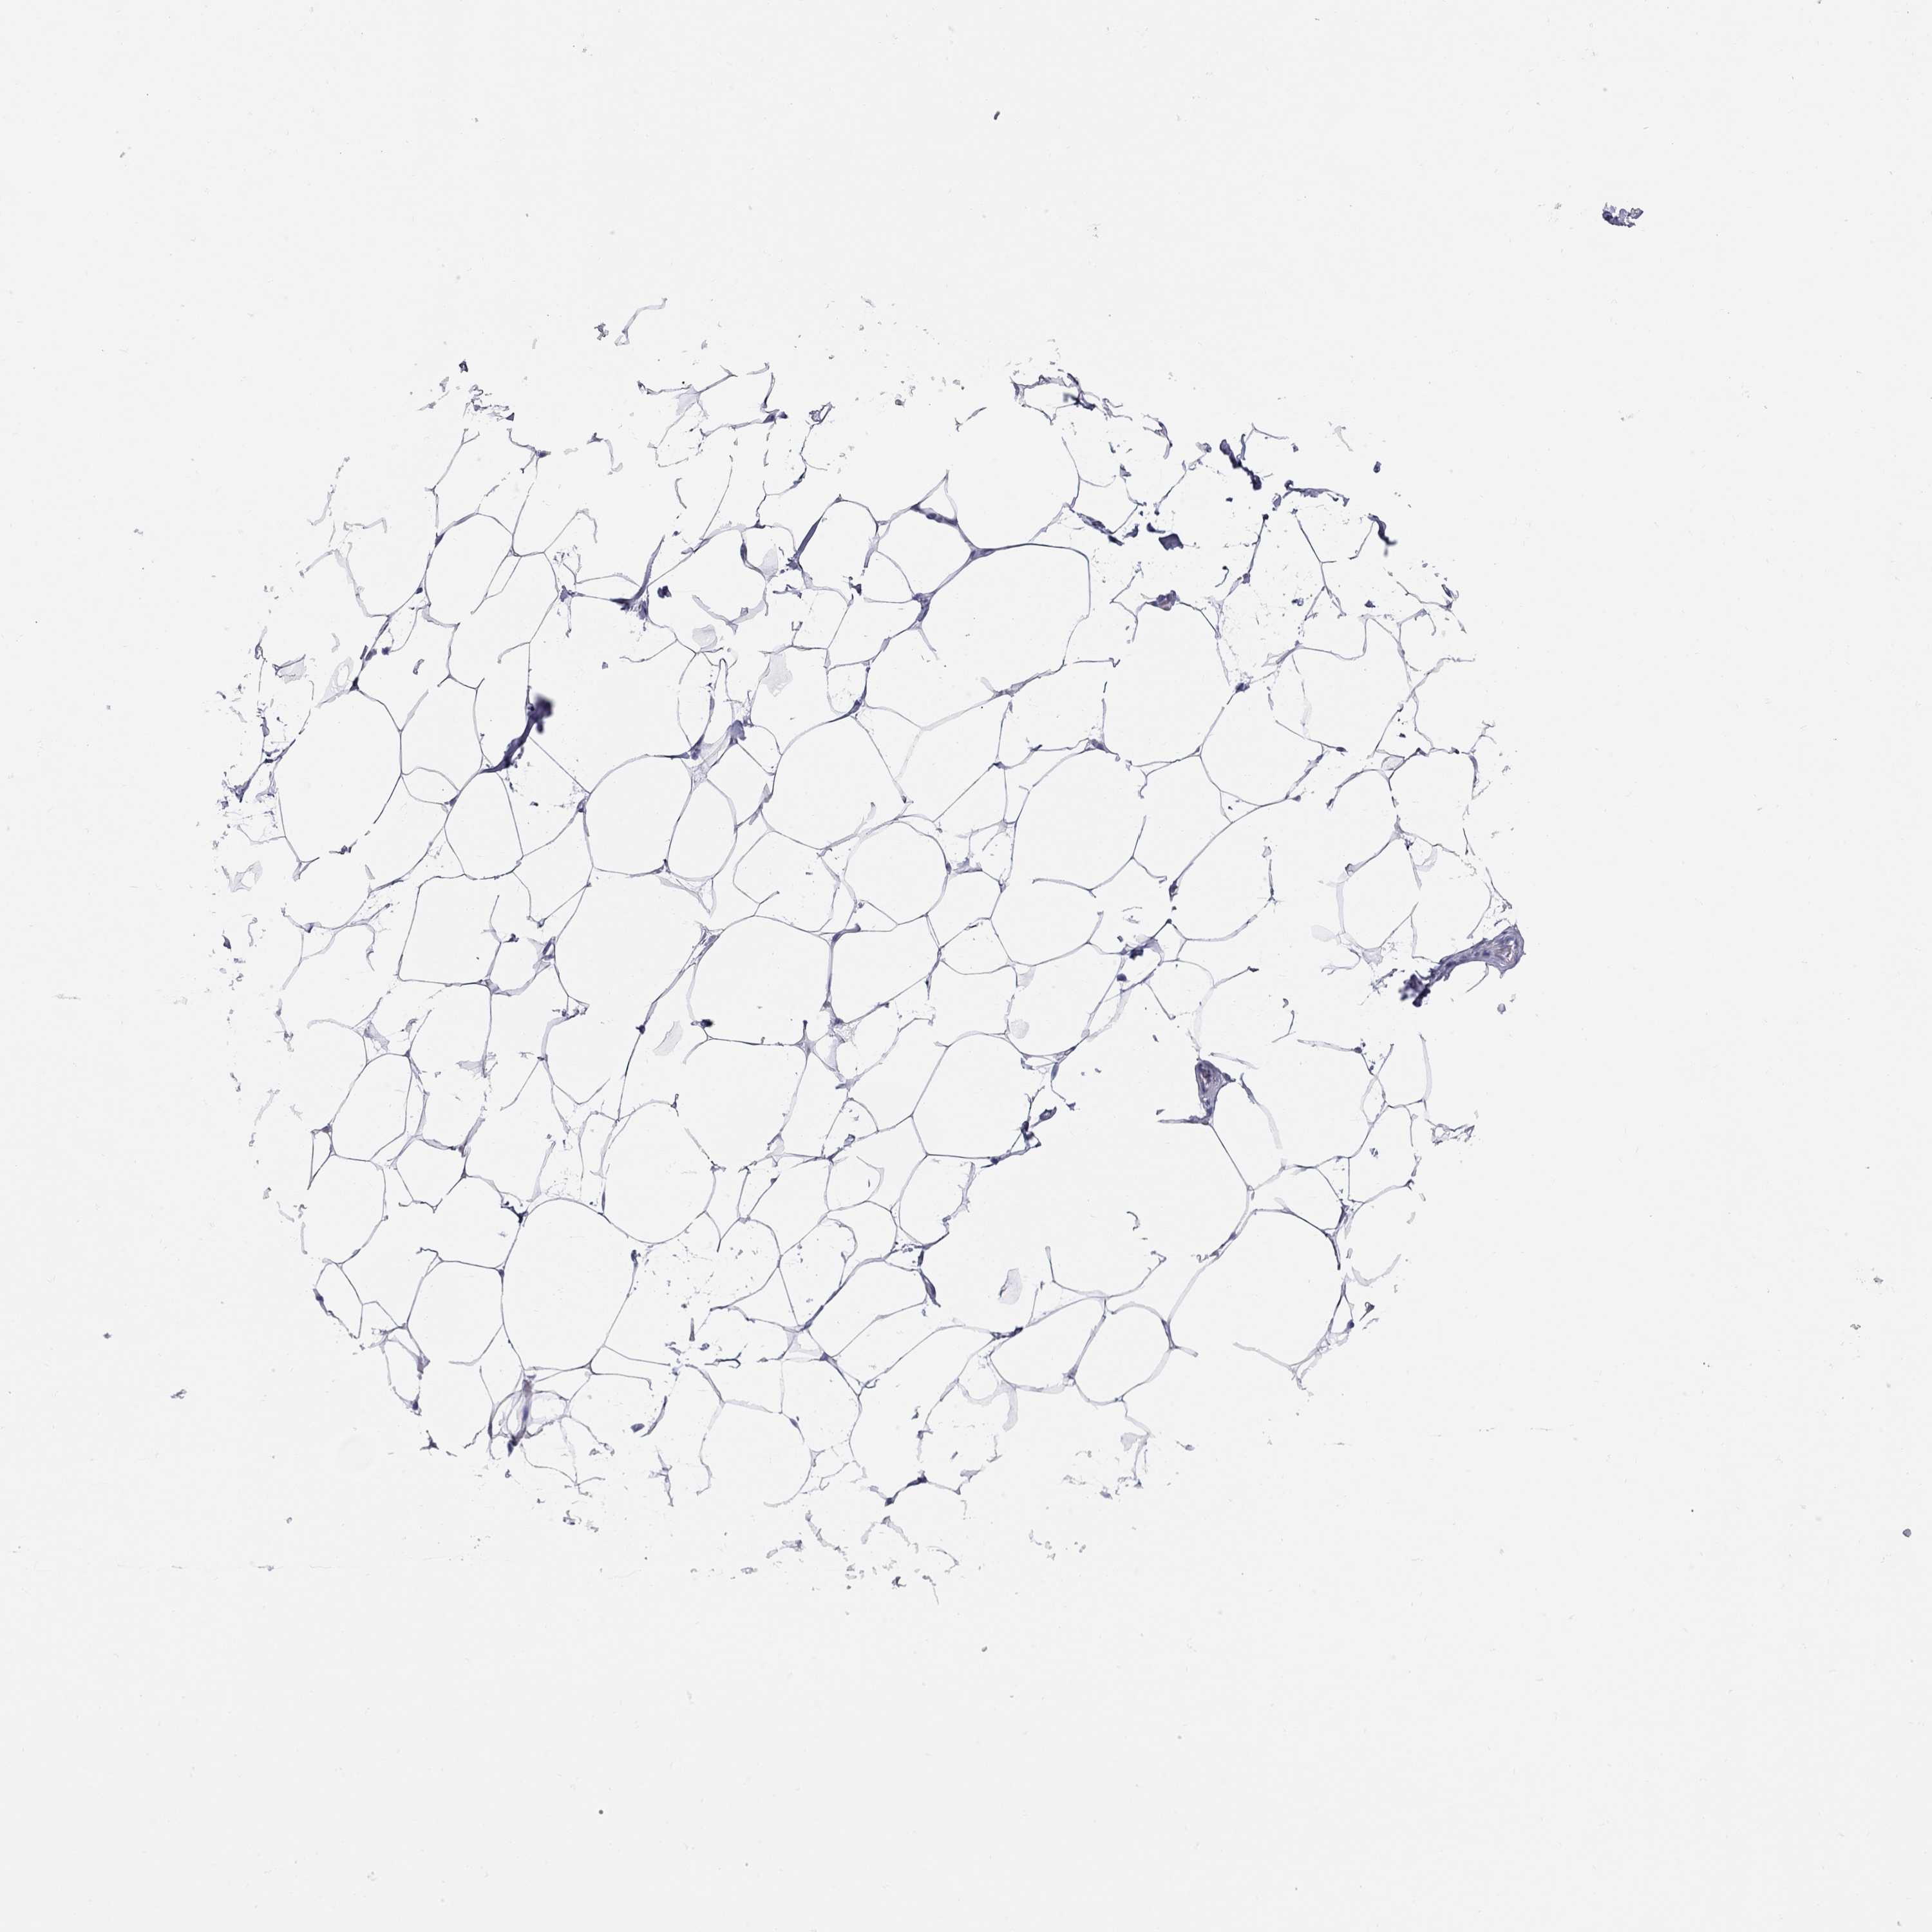

Antibody HPA020098

Adipocytes Not detected

Glandular cells Medium

Myoepithelial cells Not detected

BREAST - Antibody stainingi

Antibody staining in the annotated cell types in the current human tissue is reported as not detected, low, medium, or high, based on conventional immunohistochemistry profiling in selected tissues. This score is based on the combination of the staining intensity and fraction of stained cells.